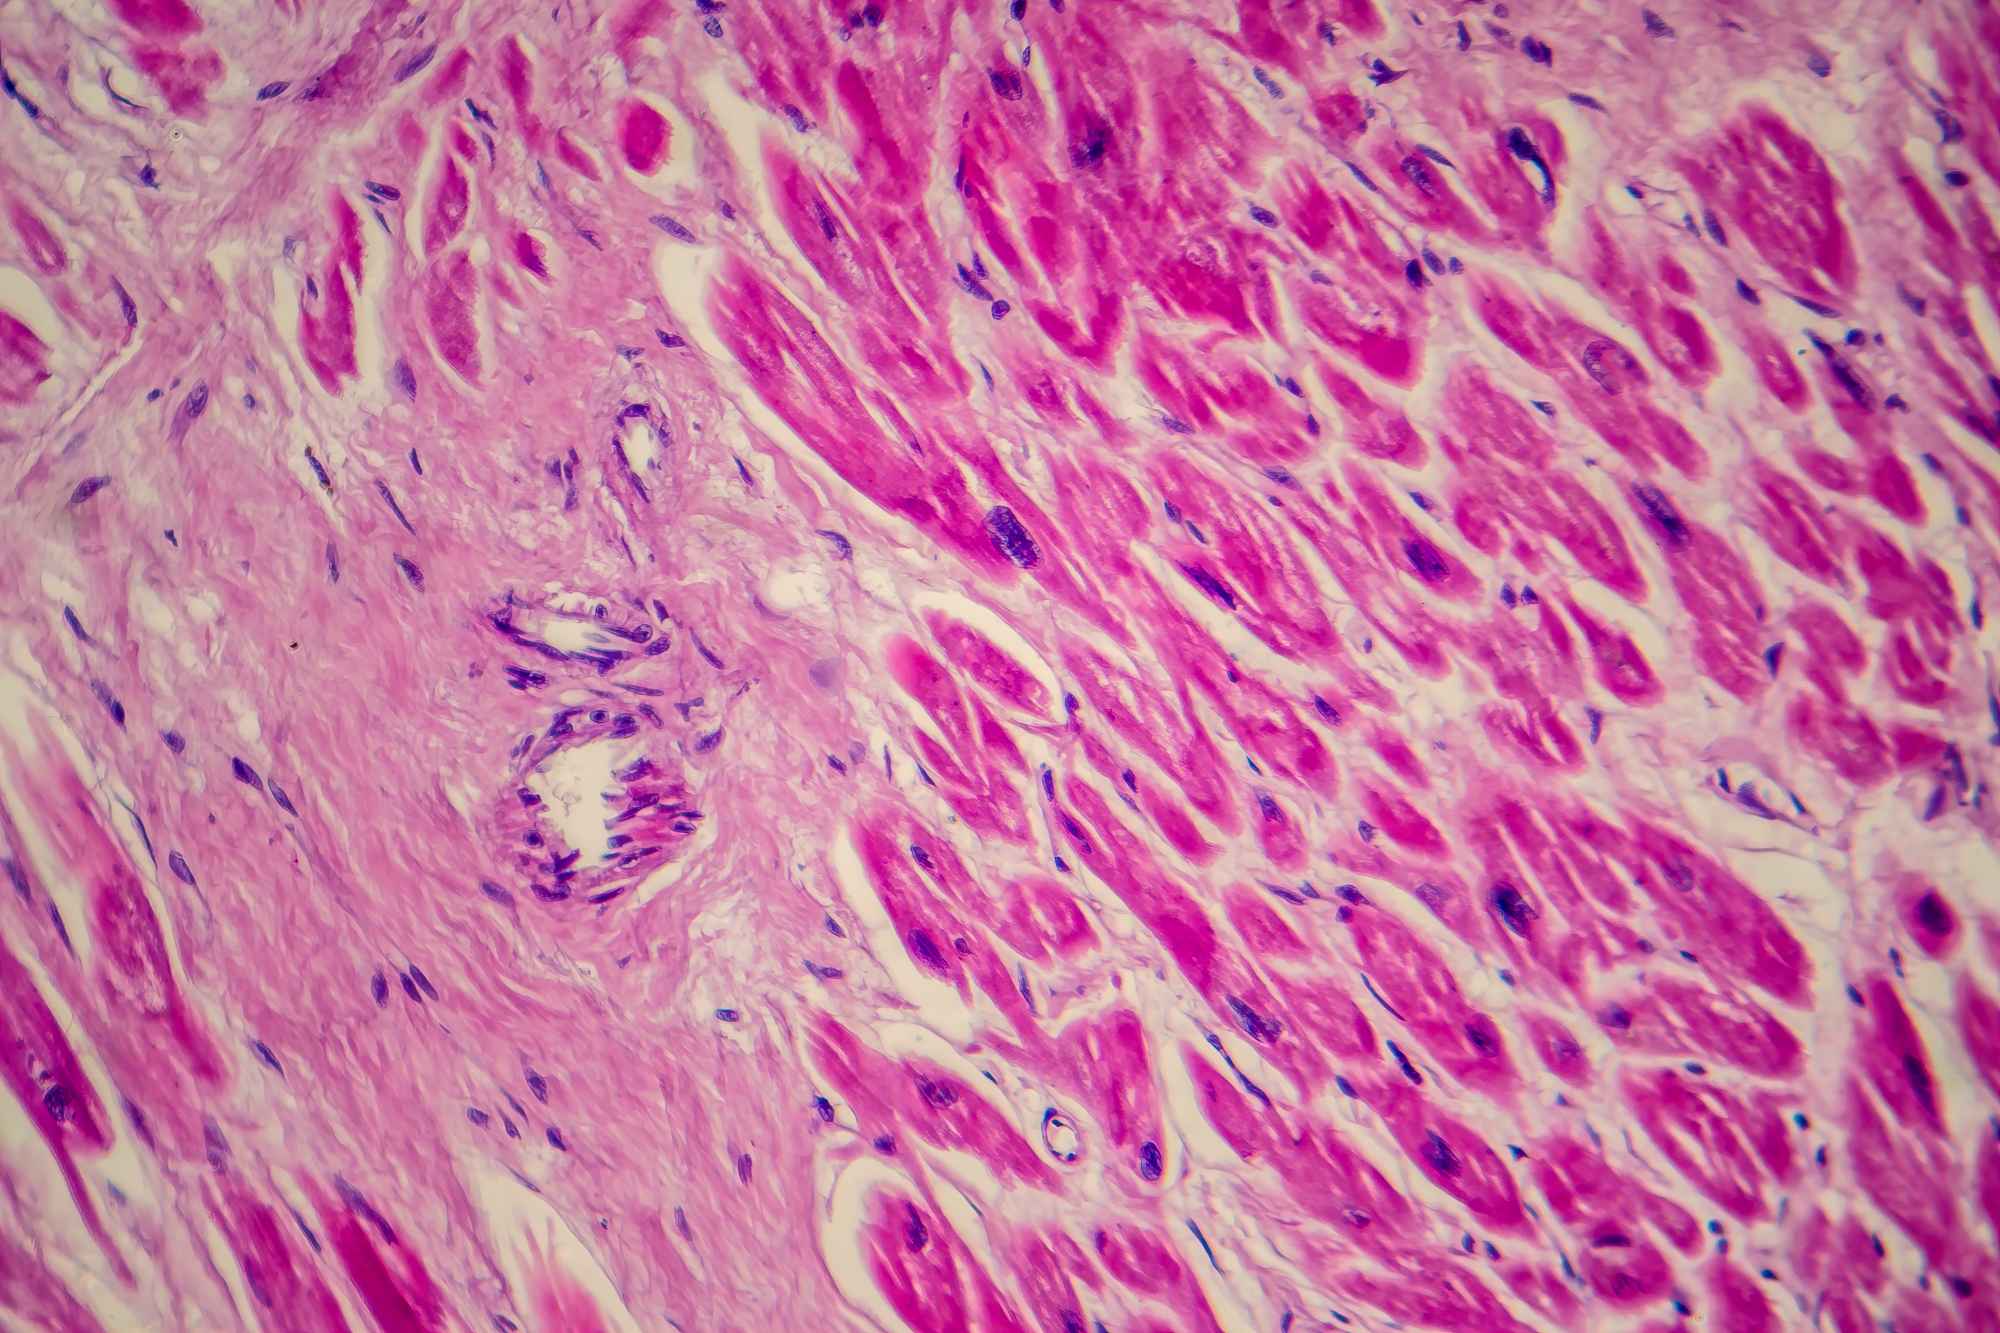

Estudian el oncogenoma de los gatos y lo comparan con el de los humanos

Aunque el cáncer es una causa común de muerte en los gatos domésticos, se sabe poco sobre la variedad de los genes afectados y cómo se comparan con el oncogenoma en las personas. Un estudio publicado en Science ha secuenciado los genes cancerígenos en 493 muestras de 13 tipos diferentes de cáncer felino para obtener una imagen más clara del oncogenoma felino. También se han comparado los genes con mutaciones cancerígenas conocidas en los seres humanos.